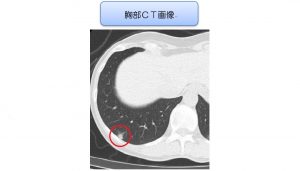

%e8%83%b8%e9%83%a8%ef%bd%83%ef%bd%94%e7%94%bb%e5%83%8f%e7%97%87%e4%be%8b%ef%bc%92